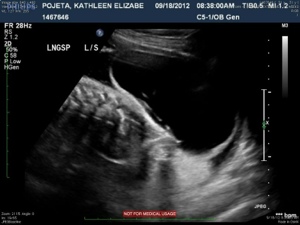

This image shows the bottom portion of the spine (lumbar and sacral). The large black area surrounded by a jelly-bean type shaped white line is the cyst, or sac.

20120921-213507.jpg